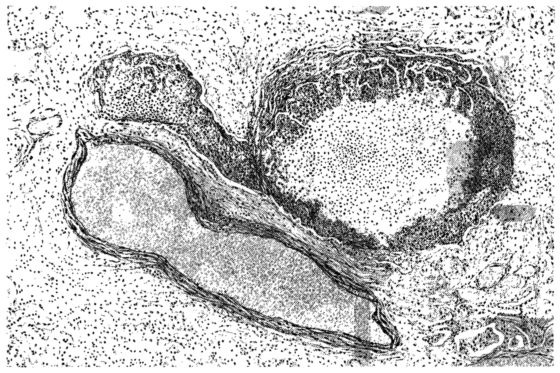

FIG. I. AUTOPSY NO. 99. ACUTE HEMORRHAGIC AND ULCERATIVE LARYNGOTRACHEITIS.

FIG. II. AUTOPSY NO. 98. DRAWING OF A SECTION THROUGH A TRACHEA SHOWING NECROTIZING HEMORRHAGIC INFLAMMATORY PROCESS OF THE MUCOSA.

The changes are less marked, perhaps, in the trachea than in its finer ramifications. The mucosa is constantly more or less destroyed and large areas, usually focal, are entirely devoid of their epithelial covering. This is replaced by a sparse exudate, composed largely of red blood cells, mucus, a small amount of fibrin, and nuclear fragments (Fig. II). It may dip into the submucosa for a short distance, but usually these indentures are associated with the ducts of the mucous glands into which the inflammatory reaction extends. A more striking feature than the exudate, however, is the edema and the congestion of the submucosa. The loose areolar tissue of the submucosa is spread widely apart, and throughout it distended blood vessels are very conspicuous. Occasionally such a vessel is broken and actual hemorrhage appears in the submucosa. Occasionally, too, the inflammation extends down the duct to the mucous gland itself, and here, also, aplastic inflammatory reaction is evident, inasmuch as the acini now stain intensely red with the cells undifferentiated from each other and specked here and there by broken remains of the dead nuclei (Fig. III). After the disease has continued for a short period, even at the end of five or six days, some regeneration of the epithelial lining may be seen (3) (Fig. IV). But despite this, the acute picture persists, and there goes on, side by side, an attempted repair characterized by epithelial regeneration and the same evidence of acute change. Since the lesion is essentially a superficial one, scars or contractures of any extent are not encountered in the trachea, even in examples of the disease that have ended fatally only after many weeks.[4]